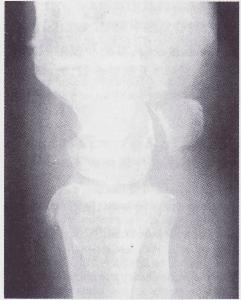

X線正位片顯示,脫位的月骨呈三角形(正常月骨應為四方形)。且投影與頭狀骨下端重疊。側位像顯示,月骨脫向掌側,半月形凹面也轉向掌側。